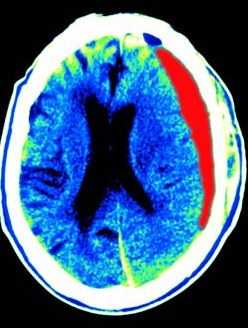

МРТ головного мозга. Т1-взвешенная аксиальная МРТ. Субдуральная гематома. Цветовая обработка изображения.